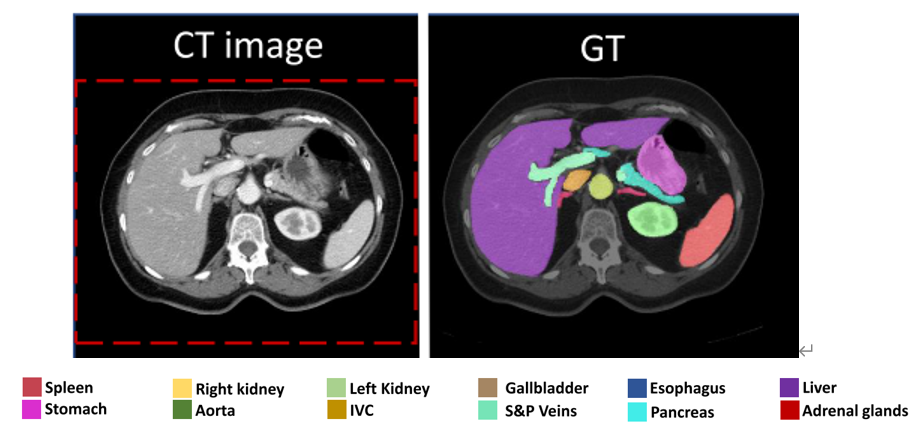

BTCV数据集来自医学全能分割比赛中,脏器分割的挑战任务。其中,输入图像包含1个通道,即CT电子密度图像,标签图像包含14个通道(13种器官加上背景点的分割)。分割任务可由下图表示,其中可以看出,原始图像的对应GT中 各个脏器已经进行了人工标记。